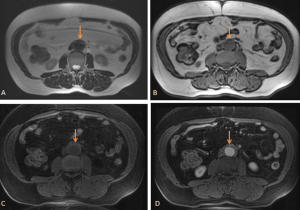

MULTIDETECTOR COMPUTED TOMOGRAPHY (MDCT)

MDCT may fail to demonstrate abnormalities in approximately one third of surgically proven RPF cases.

RPF typically appears as a well-defined, irregular paraspinal soft-tissue mass, isodense to the psoas muscle and without lateral extension beyond it. Most often centred at L4–L5 near the aortic bifurcation, it may extend cranially towards the renal hila or, less commonly, caudally to involve pelvic structures. Baseline Hounsfield units (HU) values and the diameter of the retroperitoneal tissue can assist in assessing inflammatory activity. [1,3,5-8]